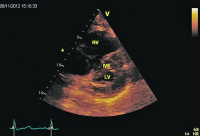

Parasternaler Längsschnitt

Abbildung 1: Parasternaler Längsschnitt: Kleiner hyperkontraktiler linker Ventrikel. Leichte Klappensklerose. Dilatation und Hypokontraktilität des rechten Ventrikels.